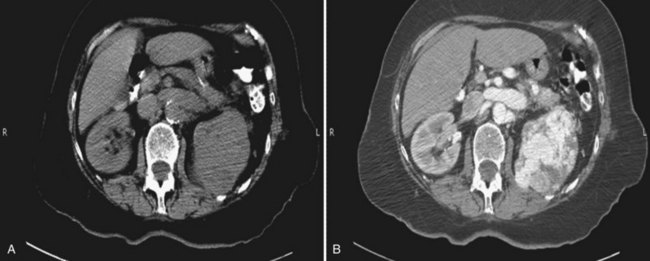

Proposed benefits of preoperative RAE include shrinkage of an arterialized tumor thrombus to ease surgical removal, reduced blood loss, facilitation of dissection due to tissue plane edema, ability to ligate the renal vein before the renal artery at time of nephrectomy, and modulation of the immune response (Klimberg et al, 1985; Bakal et al, 1993; Kalman and Varenhorst, 1999; Schwartz et al, 2007; Wotkowicz and Libertino, 2007; Wszolek et al, 2008). Ligation of the renal vein before the renal artery is useful in the setting of hilar tumors, tumors with significant medial extension, or considerable perihilar adenopathy (Schwartz et al, 2007; Wotkowicz and Libertino, 2007; Wszolek et al, 2008). Before ligating the renal vein, one should characterize the completeness of embolization to prevent unnecessary blood loss in cases of incomplete embolization. In the senior author’s experience this assessment can be made by evaluating renal venous return during surgery. In addition, angioembolization can also be useful for renal tumors associated with large arteriovenous malformations that are having a deleterious hemodynamic impact (Figs. 54-16 and 54-17).

Figure 54–16 Noncontrast (A) and contrast-enhanced (B) CT images of a patient with high output cardiac failure secondary to arteriovenous malformation associated with left renal cell carcinoma. Notice the equal contrast intensity of the aorta, left renal artery, and left renal vein.

Figure 54–17 A, Left selective renal angiogram demonstrates immediate filling of the renal vein and inferior vena cava. B, Angiogram after placement of coils demonstrates complete angioinfarction. Contrast medium in the contralateral renal pelvis confirms contralateral renal function.